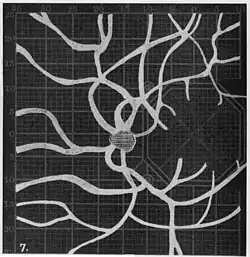

Angioscotomas were first discovered and mapped out by John Norris Evans (1891-02-28--1953-04-08)[2] in 1926, who coined the term angioscotometry to describe the painstaking charting of the scotoma of the retinal blood vessels by manual perimetry. He seated each subject in a seat in a dark setting, and tested whether they could see a tiny bright test object placed at various locations.[3] Using a 1.5 mm white disk, Evans reported intricate branch‑like scotomas that mirrored the arteries and veins emerging from the optic disc, with a full map requiring up to 2 hours to complete. He plotted this for subjects under various conditions, such as while holding breath, with glaucoma, etc. A year later, he confirmed that only short stump‑like scotomas had been noticed previously, some further data plotted with a smaller 1 mm stimuli, and under varying conditions on the subject.[4] He published a monograph on this in 1938 in which he described its use in assisting diagnosis of various conditions, such as retinal edema, glaucoma, optic neuritis, etc.[5]

In the 1940s there were further developments. Evans reviewed the state of research in 1942.[6] In 1945, Welt designed a portable campimeter and linked the size of both the blind spot and the angioscotoma to retinal arterial pressure.[7] In the same year, Weekers and Humblet published detailed tracings that overlaid vessel photographs onto Bjerrum screen plots, firmly establishing the one‑to‑one correspondence between vascular anatomy and scotoma shape.[8]

Using eccentric fixation, the more nasal parts of the angioscotoma can be plotted. -

Widening of angioscotoma under various conditions (holding head lower than trunk; holding the breath; making digital pressure on the same eye; (a vein) on opposite eye; (an artery) on opposite eye).